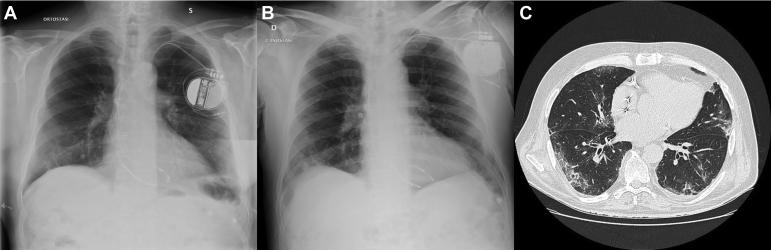

Syncope as the presenting symptom of COVID-19 infection.

HeartRhythm Case Rep. 2020 May 5;6(7):363-366. doi: 10.1016/j.hrcr.2020.04.015. eCollection 2020 Jul.

Syncope as the presenting symptom of COVID-19 infection.晕厥作为新型冠状病毒肺炎感染的首发症状